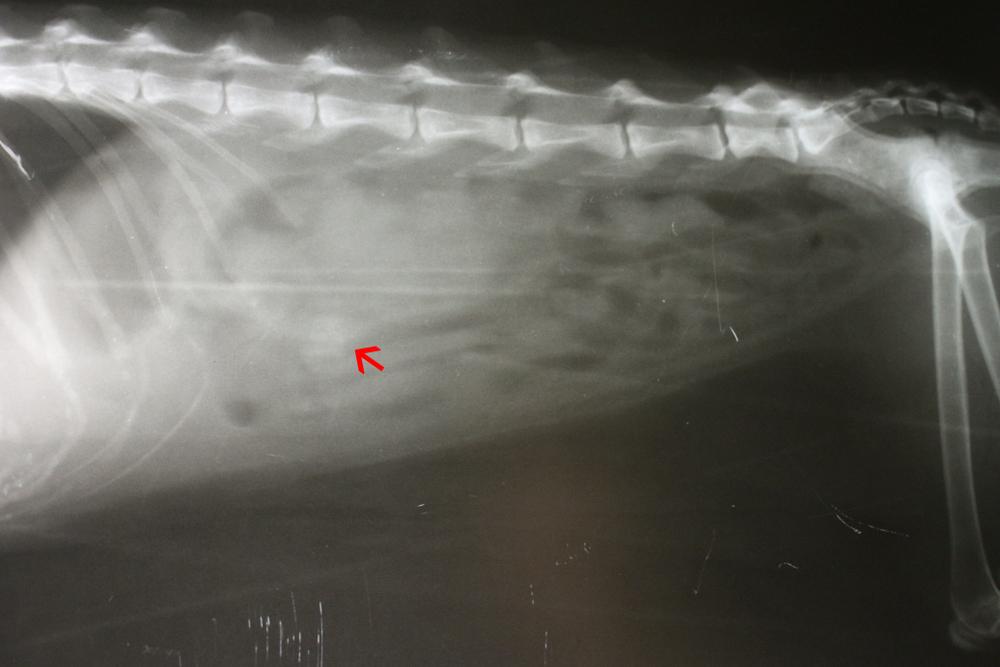

Главная опасность трихобезоаров – закупорка кишечника. Слишком большие образования забивают просвет, препятствуя выведению фекалий и провоцируя воспаление. Без своевременной помощи животное может погибнуть от перитонита в результате разрыва кишечных стенок или острой интоксикации на фоне отравлениями продуктами своей жизнедеятельности.

Если попытки срыгивания не приносят результата, а рвота участилась – обратитесь к ветеринарному врачу. Такое состояние развивается при закупоривании просвета кишечника слишком плотными и крупными трихобезоарами. При наличии опасности отмечаются следующие сопутствующие симптомы:

Медлить при таких симптомах нельзя. Проблема решается строго хирургически, поэтому ни в коем случае не тратьте время на самолечение.

После проведения диагностики трихобезоар извлекают либо во время эндоскопии, либо с помощью полостной операции. Для облегчения опорожнения используют вазелиновое масло. Оно не всасывается и полностью выводится из организма вместе с калом, что исключает передозировку.